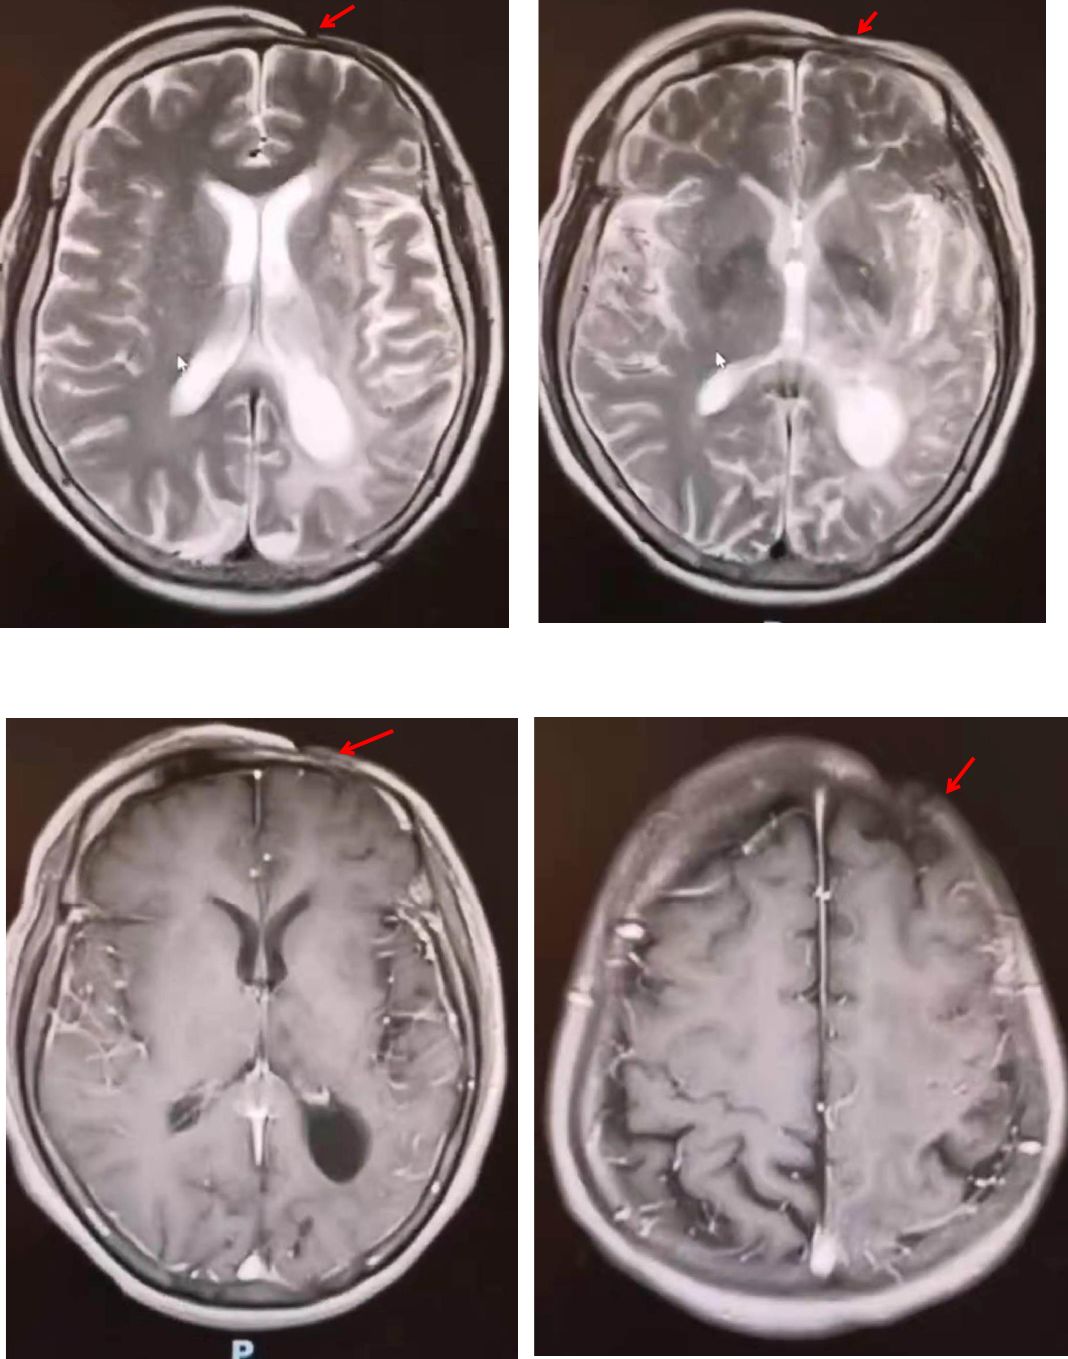

病例7

52岁,男性,头晕20余天,伴言语不利、智能下降。患者自述于20余天前无明显诱因下出现头晕,呈持续性头重脚轻感,无明显规律,伴有言语欠流利、智能下降,表现为计算力、理解力、记忆力下降,偶有咳嗽、呈阵发性单声咳,咳少许白色粘痰;间断发热,最高体温38.5℃。影像学如下:

影像学可见双侧颞、顶叶及右侧额叶多发散在皮层下白质病变,长T2,DWI高信号,ADC高信号。疾控中心HIV-1抗体:阳性,CD4+64cell/ul。

诊断: HIV相关脑病(HIV相关痴呆)

病例讨论:

根据当前针对HIV相关神经认知障碍(HIV-associated neurocognitive disorder,HAND)的国际“Frascati”分类标准,可分为无症状性(ANI),轻度认知障碍(MND)和HIV痴呆(HAD)三个阶段。ANI为量表提示有认知域损害,但日常生活能力无影响;MND轻度的认知功能障碍且影响日常生活能力轻度受损;HAD为明显认知障碍且日常生活能力明显受损。(Neurology. 2007 Oct 30; 69(18):1789-99.)

艾滋病相关性痴呆在 20% 的 AIDS患者中发生,往往是HIV感染缓慢进展数月后出现的迟发表现,这类患者CD4+细胞>350/μl。

HIV相关痴呆与 “皮质型”痴呆如阿尔茨海默不同,前者较少出现失写、失算、失用等皮质功能障碍。一些研究者称其为皮质下痴呆,表现为短期记忆和执行功能损伤。

脑部 MRI 显示萎缩和广泛白质改变。运动障碍也可单独发生或伴随 HIV引起的痴呆一同发生发展。HIV 感染者中运动障碍的发生率为 3%。

其影像学表现常位于白质,如脑室旁、半卵圆中心,呈对称、弥漫、云雾样白质异常,病灶可延伸至灰白质交界处。

看两例文献图:

Case1:

Case2:

图自:Topics in Magnetic Resonance Imaging .Volume 23, Number 5, October 2014

回到该病例,无论临床及影像学,除需要进一步完善认知功能评估之外,尚需要与进行性多灶性白质脑病(PML)相鉴别。PML是由JC病毒侵犯免疫抑制的HIV患者导致的中枢神经系统感染。影像学特点是以顶叶为主的皮层下白质散在受累,并呈融合趋势,会累及U形纤维是其特点之一。